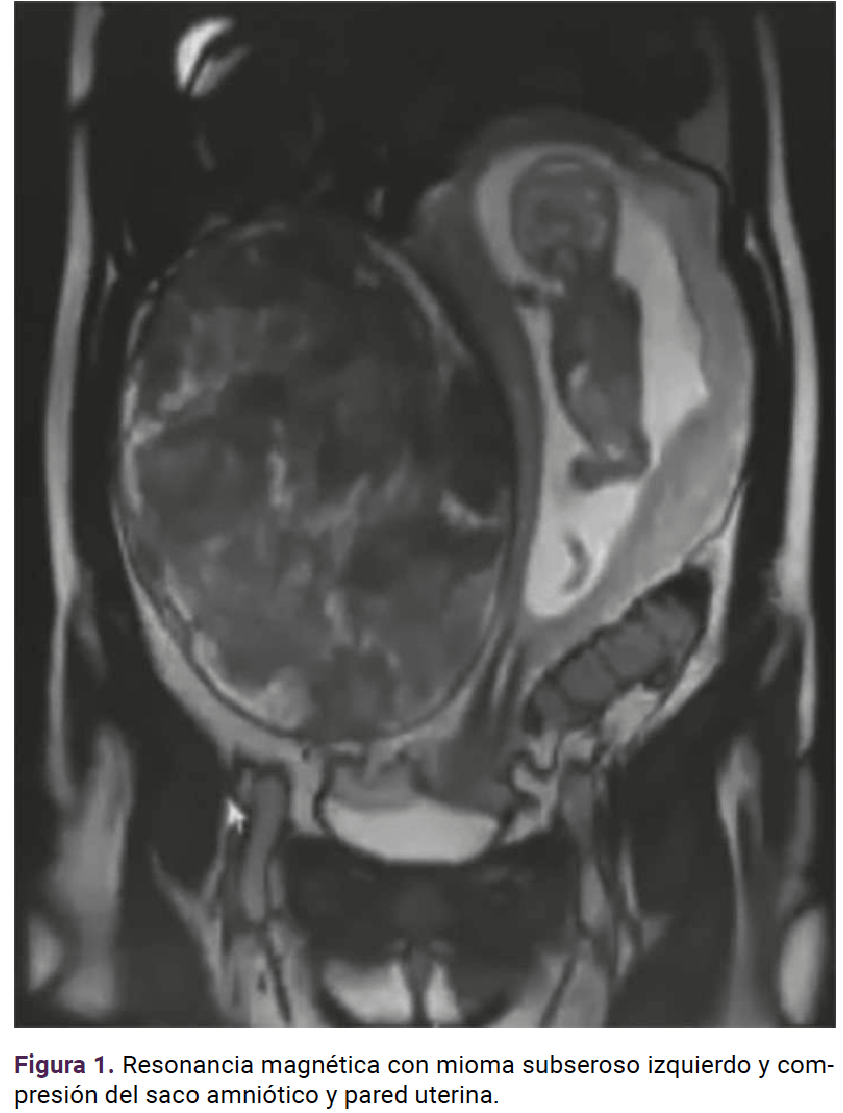

Paciente de 19 años, primigesta, con antecedente heredofamiliar (tía paterna) de cáncer de ovario. Acudió a consulta para control prenatal a las siete semanas de gestación, con dolor abdominal y crecimiento rápido de un tumor abdominal. Durante la exploración física el abdomen se palpó globoso, a expensas del tumor abdominopélvico, a 2 cm por arriba de la cicatriz umbilical, móvil, con dolor a la palpación media y profunda. El ultrasonido reportó un mioma subseroso de 15.4 x 7.3 cm y la resonancia magnética concluyó que se trataba de un mioma con diámetro mayor de 24 centímetros que desplazaba y comprimía la cavidad amniótica (Figura 1). En la interconsulta con el ginecooncólogo se planteó la posibilidad de complicaciones conforme el mioma fuera creciendo; por ello se decidió la miomectomía abierta en el segundo trimestre de la gestación. La miomectomía se llevó a cabo, sin ingreso a la cavidad uterina, a las 21.4 semanas y se extirpó un mioma intraligamentario de 20 x 18 x 11 cm y 2410 g (Figuras 2, 3 y 4) con sangrado de 900 mL y las dificultades propias de un mioma hipervascularizado. El estudio transoperatorio reportó: leiomioma con cambios hidrópicos, negativo para malignidad (mismo diagnóstico del reporte definitivo). Se finalizó el procedimiento y se corroboró la frecuencia cardiaca fetal de 150 lpm. El resto del control prenatal transcurrió sin complicaciones y se finalizó el embarazo a las 38.0 semanas mediante cesárea, indicada por registro cardiotocográfico categoría II (línea basal con bradicardia con mínima variabilidad y ausencia de aceleraciones), sin complicaciones, con sangrado de 300 mL y obtención de una recién nacida de 2515 g, Apgar 8-9. A petición de la paciente se le colocó un dispositivo intrauterino de levonorgestrel, como método de control de la fertilidad.

<strong>Figura 4</strong>

Figura 4.